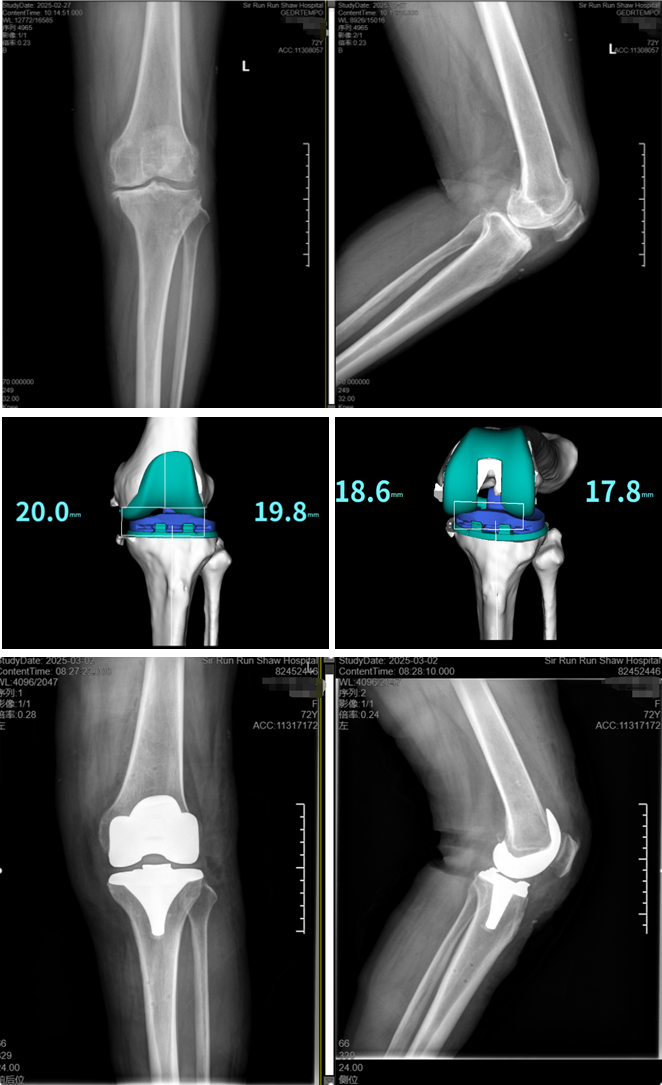

首台机器人辅助全膝关节置换手术

患者J女士,今年72岁,因“双膝疼痛伴活动受限十年,左侧重”入院行全膝关节置换术。骨科团队充分利用了机器人的智能手术规划系统,根据患者的个体特征进行了精准的手术规划,并利用ARTHROBOT可视化、数字化和精准化的优势,通过实时导航与机械臂操作,仅用20分钟完成膝关节精准截骨和假体安装,假体安装位置与规划完全一致,实现了功能学对线和膝关节间隙平衡,手术全程出血量少,软组织损伤小,并提高了手术效率。

患者术后次日即可在助行器辅助下床活动,疼痛明显缓解。J女士感慨:“现在膝盖不疼了,走路也稳了,终于能够恢复正常生活了!” 施培华教授表示,机器人可以为患者提供定制化的手术规划,实现功能力学定线,术中可根据患者的软组织平衡情况调整截骨量和截骨角度,减少对软组织松解的需要,此技术不仅提升了手术精准度,降低了术后感染、假体松动等并发症风险,还可以加快术后康复,并为复杂膝关节疾病患者提供更优解决方案。